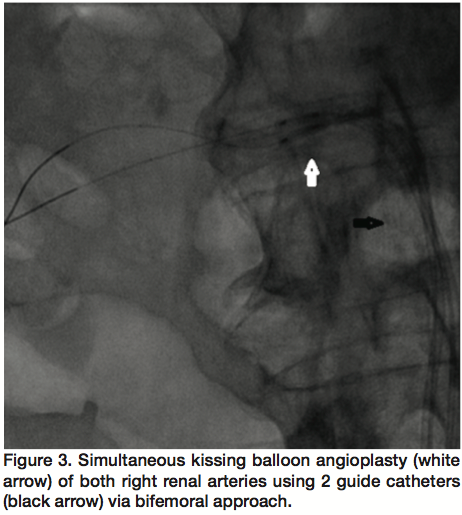

Selective renal arteriography revealed a solitary left renal artery with mild stenosis. However, the right kidney had a dual arterial supply, superior and inferior right renal arteries. Ostia of the 2 renal arteries were very close, but selective arteriography could not be performed using one catheter at a time, and each one had to be engaged separately. Both the superior (Figure 1) and inferior (Figure 2) renal arteries had an ostial 95% stenosis, with a pressure gradient of 70 mm Hg. Each artery supplied almost half the kidney, and there was no true “dominant” artery. Interestingly, the 2 ostia were too close to allow for simultaneous engagement even using 2 catheters.